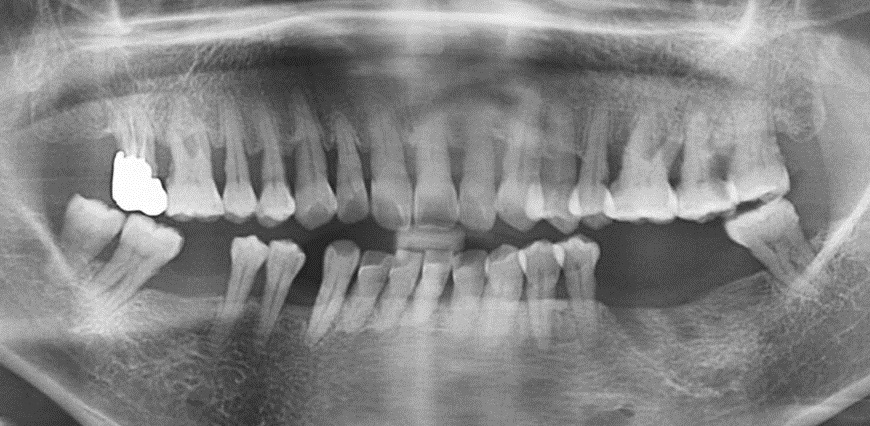

Panorama taken at the initial visit severe vertical bone resorption has been appreciated on the right posterior maxilla